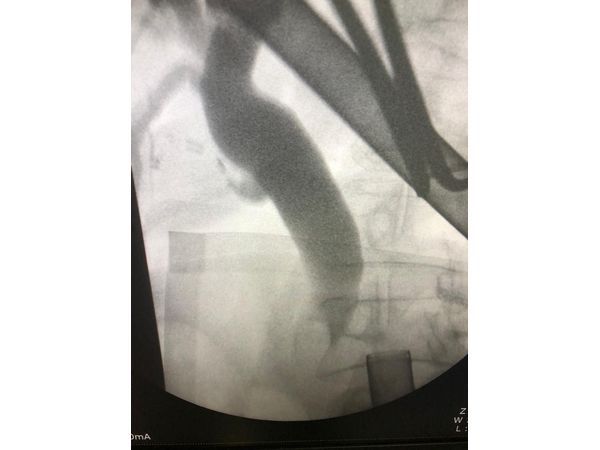

- Интраоперационную фистулохолангиографию — в желчные протоки ввели контрастное вещество, затем сделали рентгеновские снимки. Так подтвердили наличие крупного конкремента.

- Ретроградную холангиопанкреатографию с эндоскопической папиллотомией и холедохолитоэкстракцией. В ходе этой манипуляции через рот и пищевод в двенадцатиперстную кишку ввели гибкую трубку. Через неё пустили контрастное вещество и сделали рентгеновские снимки протоков желчного пузыря и поджелудочной железы. После этого рассекли проток, в котором находился камень, и извлекли конкремент.